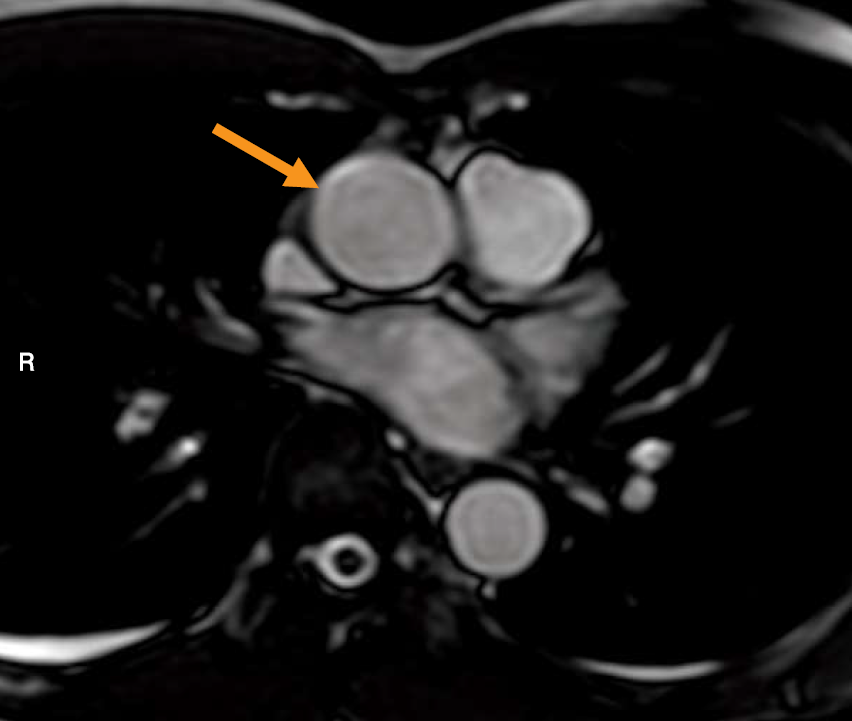

胸部MR像を示す。矢印で示す血管と直接交通しているのはどれか。

この画像は、心臓の付け根(心基部)あたりを横断するMRI像です。矢印は、体の中で最も太い動脈である上行大動脈を指しています。 この大動脈が、心臓のどの部屋と繋がっているかを理解するには、心臓全体の血液の流れ(血流ルート)を思い浮かべることが重要です。

このルートから、大動脈(矢印)に血液を直接送り出しているのは、左心室であることが分かります。

- 矢印は上行大動脈。ここに血液を送り出すのは、最も強力なポンプである左心室である。

- 横断像での位置関係の鉄則は、「右心室は最も前方、左心房は最も後方」。